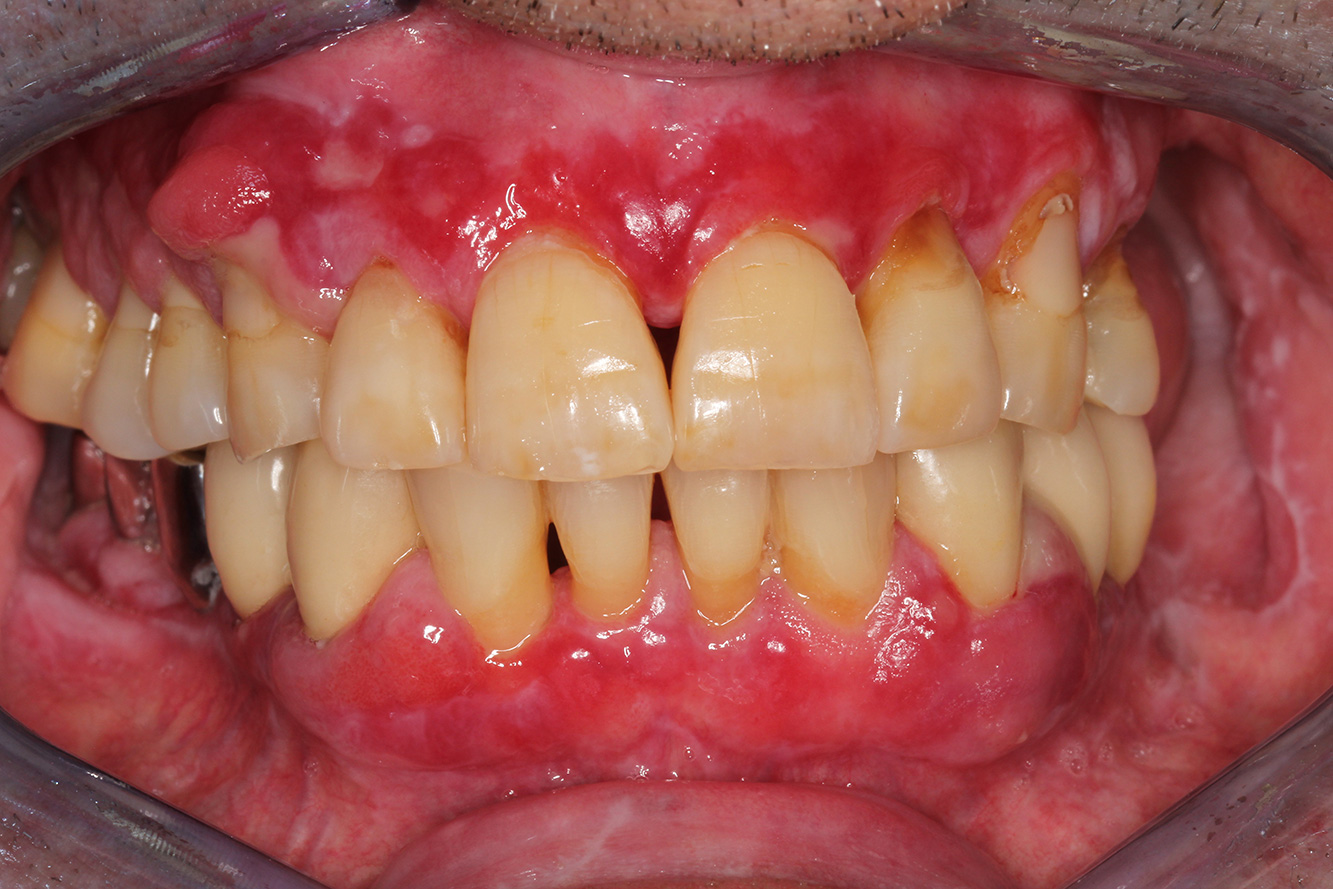

Der Transplantationspatient mit Gingivawucherungen

Ein 71-jähriger Patient mit Z.n. Nierentransplantation und Hypertonie (Bluthochdruck) stellt sich vor. Bedingt durch die Krankengeschichte ist eine Dauermedikation mit Cyclosporin, zur Unterdrückung der Immunabwehr, und Amlodipin, zur Blutdrucksenkung, erforderlich. Außerdem berichtet der Patient über empfindliches Zahnfleisch und Zahnfleischbluten. Aus mundgesundheitlicher Sicht zeigt sich ein saniertes Gebiss mit acht fehlenden Zähnen, ausgeprägte Gingivawucherungen, eine Parodontitis Stadium II, Grad B mit aktiven Taschen und eine initiale Wurzelkaries an Zahn 22. In der Kariesrisikoabschätzung wird ein mittleres Kariesrisiko (API 60) festgestellt. Für die Prophylaxesitzung lassen sich folgende Behandlungsempfehlungen ableiten. mehr Infos